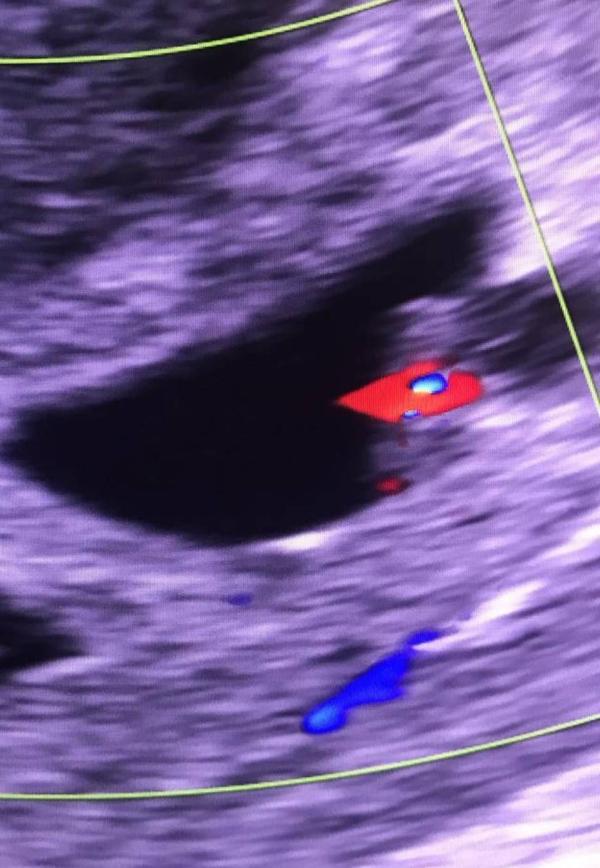

Сегодня впервые увидела и услышала сердце малютки ❤️

также сегодня сделали узи🥹🥹🥹